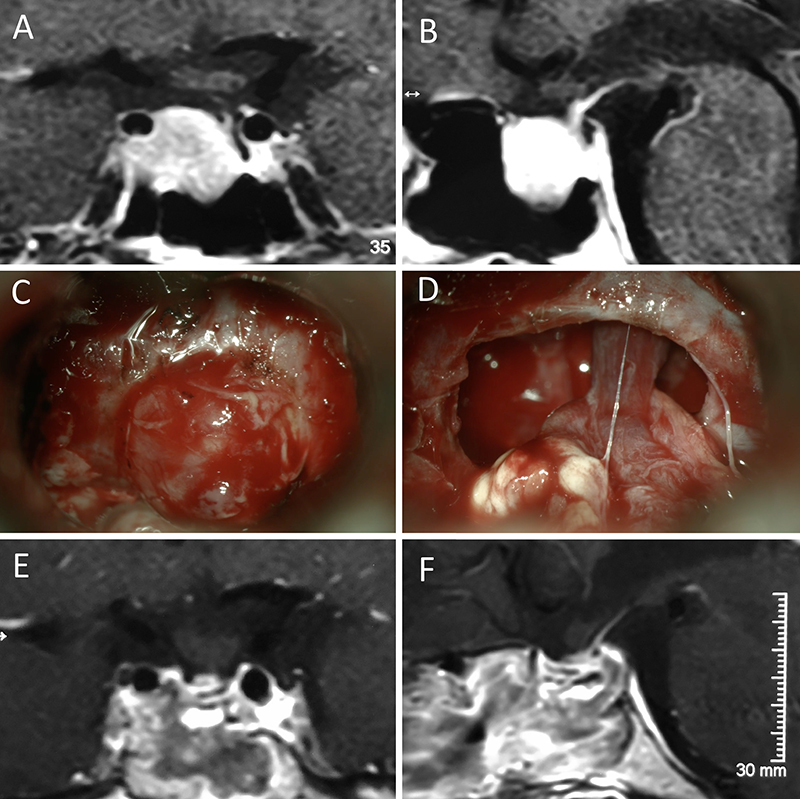

Figura 5: Apoplejía hipofisaria hemorrágica en un hombre de 32 años. El paciente presentó cefalea y parálisis completa del III par. Tuvo restitutio ad integrum en el seguimiento. A-B: RM preoperatoria; C-D: intraoperatorio; E-F: RM postoperatoria.

Figura 6: Apoplejía hipofisaria hemorrágica en un hombre de 55 años. El paciente presentó cefalea, déficit visual y parálisis completa del III par. Evolucionó favorablemente tras la cirugía, revirtiendo el cuadro. A-B: RM preoperatoria; C-D: intraoperatorio; E-F: RM postoperatoria.